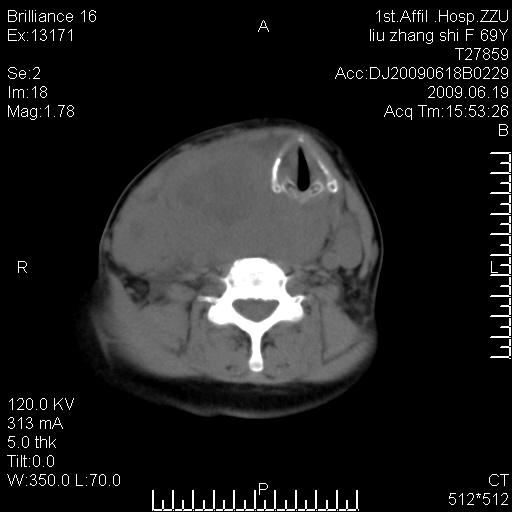

标题: CT26782:女,69岁,颈部占位,3天后公布病理结果。

【病理证实系列】女,69岁,颈部占位,有病理结果,3天后公布。(由于病例时间较久,临床资料不全,请网友见谅)本系列将有几百种常见、少见及罕见病例,均经病理证实。病例资料来自郑州大学第一附属医院。与网友共享,本人有空就发。

甲状腺癌并颈部淋巴结转移。感谢楼主的良苦用心,谢谢。

甲状腺癌并颈部淋巴结转移。

需与鼻咽癌鉴别!

支持甲状腺癌广泛侵及周围结构并颈部淋巴结转移。

鉴别:淋巴瘤、恶性神经源性病变、恶性纤维组织细胞瘤。

病理结果:颈部非霍奇金淋巴瘤。

右侧甲状腺确实有问题